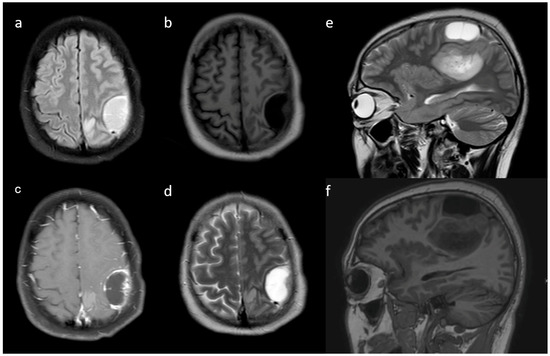

3.2. MRI Parameters of IDH-Wildtype vs. Mutant Phenotype Tumors

| Variable | Parameter | IDH-Mutated (n = 19) | IDH-Wildtype (n = 129) | p-Value |

|---|---|---|---|---|

| Enhancement I | Mild | 9 (47.4) | 5 (3.9) | <0.001 |

| Moderate | 6 (31.6) | 25 (19.4) | ||

| Severe | 4 (21.1) | 99 (76.7) | ||

| Enhancement III | Rim | 6 (31.6) | 104 (80.6) | <0.001 |

| Nodular | 0 | 2 (1.6) | ||

| Patchy | 11 (57.9) | 13 (10.1) | ||

| Solid | 2 (10.5) | 10 (7.8) | ||

| Necrosis | None | 3 (15.8) | 3 (2.3) | <0.001 |

| <25% | 11 (57.9) | 14 (10.9) | ||

| 25- 50% | 2 (10.5) | 35 (27.1) | ||

| >50% | 3 (15.8) | 77 (59.7) | ||

| Dural enhancement | AbsentPresent | 07 (70.0) | 31 (24.0)48 (52.7) | 0.013 |

| Edema | None | 3 (15.8) | 3 (2.3) | 0.025 |

| <tumor volume | 11 (57.9) | 68 (52.7) | ||

| Equal to tumor volume | 4 (21.1) | 35 (27.1) | ||

| >tumor volume | 1 (5.3) | 23 (17.8) | ||

| Cysts * | No | 11 (57.9) | 115 (89.1) | 0.001 |

| Yes | 6 (31.6) | 14 (10.9) | ||

| Subcortical involvement | Involved | 18 (94.7) | 94 (72.9) | 0.044 |

| Not involved | 1 (5.3) | 35 (27.1) | ||

| rCBV | Median (IQR) | 1.8 [1.4–2.0] | 2.6 [1.9–3.5] | 0.001 |